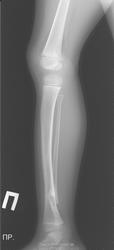

Терещенко Тимофей Денисович, 2009 года роджения, в августе 2011 года обратились в поликлинику по месту жительства в связи с уплотнением на правой голени. В результате рентгена выявлен перелом правой малоберцовой кости. При повторном контрольном обращении под вопросом был диагноз ложный сустав, в результате КТ обследования в мае 2012 года диагноз: единичная киста н/3 малоберцовой кости. В октябре 2012 года был произведен рентген и поставлен диагноз: единичная киста н/3 малоберцой кости, консолидация паталогического перелома, вальгусные стопы.

В августе 2013 на обследовании выявлено укорочение правой половины тела, единичная киста н/3 малоберцой кости, консолидация паталогического перелома.

В октябре 2013 на основании КТ обследования диагнозы:десмопластическая фиброма? метафизарный фиброзный дефект, остеокластома в ячеистой форме? Далее лечение не назначено.

Лечение в представленном Вами случае только оперативное. Оно должно быть выполнено в профильном травматолого-ортопедическом отделении детского стационара. Характер имеющихся патологических изменений костной ткани окончательно определит биопсия, произведенная во время операции. Малоберцовая кость практически не участвует в функции опоры, поэтому, если нет боли, постепенного увеличения в объеме патологического участка или изменения цвета кожных покровов над ним, рентгенологическая картина в динамике остается прежней, то операцию можно пока отложить, а ребенку понаблюдаться у ортопеда. Это решит Ваш лечащий врач.

Кстати, уважаемый Алексей Станиславович, а что Вы, как рентгенолог, думаете о большеберцовой кости справа? Не изменена ли ее ось во фронтальной плоскости в сравнении с контралатеральной стороной, и не есть ли это признак латентного ложного сустава при фиброзной дисплазии?